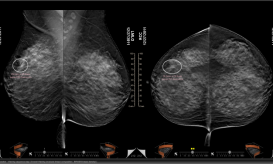

Δωρεάν ψηφιακή μαστογραφία για ανασφάλιστες στον Κορυδαλλό

Δωρεάν εξέταση ψηφιακής μαστογραφίας σε οικονομικά αδύναμες και ανασφάλιστες γυναίκες παρέχει ο Δήμος Κορυδαλλού, σε συνεργασία με τον Σύλλογο...

Πρόγραμμα δωρεάν μαστογραφιών και ενημέρωσης για τον καρκίνο του μαστού υλοποιήθηκε με την στήριξη του ΙΣΑ από την Ελληνική...